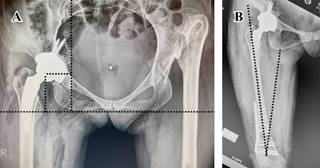

Se realiza irrigación de heridas quirúrgicas, reinserción de colgajo muscular de los glúteos con vicryl 2.0 y fascia lata con el mismo tipo de sutura, cierre de tejido celular subcutáneo y piel con punto subdérmico y misma secuencia de cierre en herida distal. Se mantiene a la paciente en posición de cubito supino, extremidad con 15o de flexión de rodilla e indicaciones de no deambular hasta nueva orden e indicación de radiografía postoperatoria (Figura 13). Durante el tiempo transoperatorio se reportó un sangrado de 300 cm3, sin tener la necesidad de transfusiones, libre de accidentes e incidentes, con cuenta de textiles completa y tiempo quirúrgico de 90 minutos; la paciente sale de la sala en estado estable. Se llevó a cabo una revisión a las tres semanas para retiro de puntos; se continua con indicación de diferir apoyo hasta presentar datos radiográficos sugerentes de consolidación, con citas subsecuentes a las cuatro, ocho, 12 y 16 semanas con controles radiográficos. Se decide apoyo parcial a las seis semanas y total a las 12. Se presentaron parestesias en el dermatomo L5 y S1, conservando integridad motora de los mismos niveles. Se observa radiográficamente consolidación a las 16 semanas por escala de Montoya. Sobre las mediciones radiográficas, observamos una recuperación nativa del CRCF, inclinación del componente acetabular de 43o y anteversión de 13o obtenida por el método de Widmer, ambos ángulos dentro de la zona de seguridad de Lewinnek, efecto Voss neutro y Offset externo de 35 mm; se observa la presencia de tornillos de fijación acetabular endopélvicos, situación esperada por las características displásicas del acetábulo al carecer de una cobertura ósea adecuada y paredes delgadas (Figura 13A); en relación a los ejes mecánicos y anatómicos, se conserva una adecuada angulación en asociación con la rodilla con un ángulo Q 18°, considerado dentro de los parámetros normales (Figura 13B).